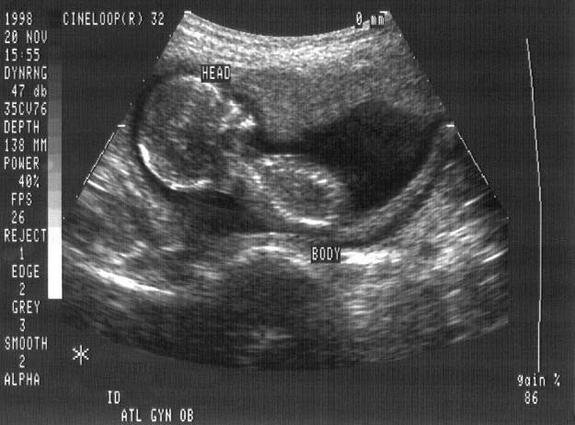

Obstetric ultrasonography is the use of medical ultrasonography in pregnancy, in which sound waves are used to create visual images of the developing embryo or fetus in the uterus. The procedure is a standard part of prenatal care in many countries, as it can provide a variety of information about the health of the mother, the timing and progress of the pregnancy, and the health and development of the embryo or fetus. The International Society of Ultrasound in Obstetrics and Gynecology recommends that pregnant women have routine obstetric ultrasounds between 18 weeks' and 22 weeks' gestational age in order to confirm pregnancy dating, to measure the fetus so that growth abnormalities can be recognized quickly later in pregnancy, and to assess for congenital malformations and multiple pregnancies. Empty your bladder 90 minutes before exam time, then consume one 8-ounce glasses of fluid about an hour before exam time. We recommend a two-piece outfit so we can access your abdomen without you removing your clothing.